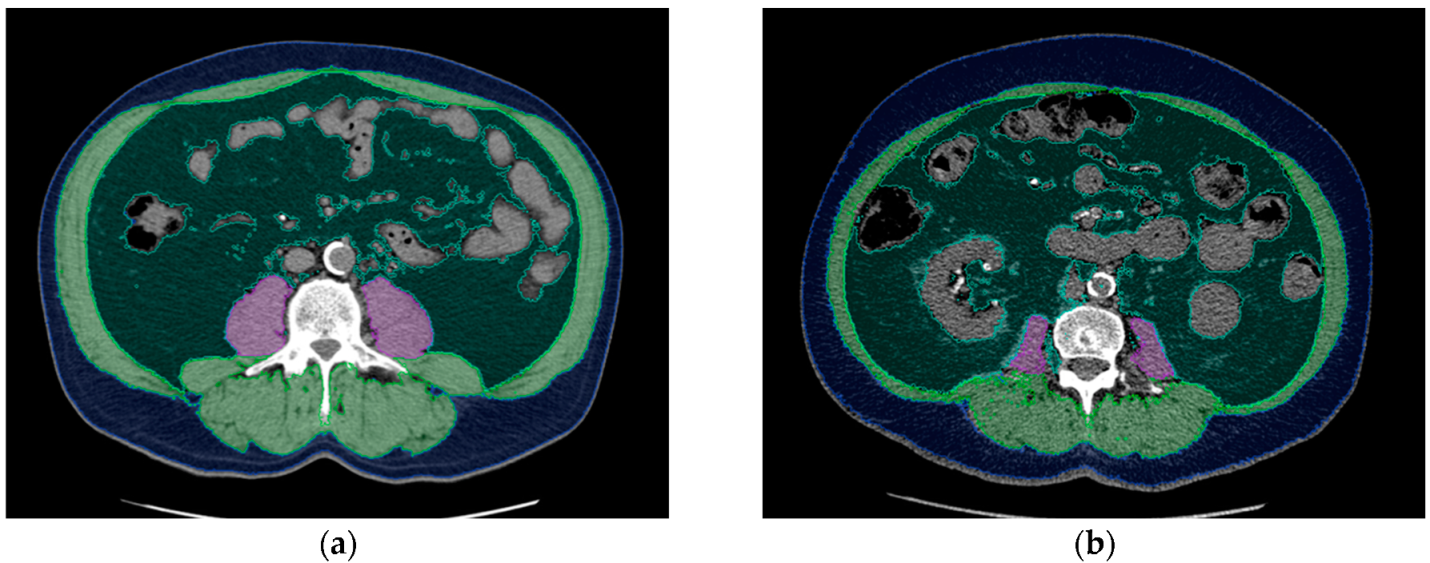

Available CT datasets acquired at the Department of Radiology and at external locations were used for analysis of body composition. Image segmentation was performed with an AI-based automated software tool using a convolutional neural network, U-net (Visage version 7.1, Visage Imaging GmbH, Berlin, Germany). The network consists of nine blocks: four down-sampling blocks, four up-sampling blocks, and one in between. The training data consisted of 200 axial CT images of the L3 level, and augmentation was applied during training to improve generalization of the network. Psoas muscle, skeletal muscle, visceral adipose tissue, and subcutaneous adipose tissue were automatically separated and coded with different colors. Automatic segmentation was checked by an experienced radiologist. In few cases, AI-based image segmentation was manually corrected, for example, when hypodense stool in the intestine was misinterpreted as body fat. The software automatically calculated the area in square centimeters (cm2) and density in Hounsfield units of each segmented tissue class. Areas of skeletal muscle, visceral adipose tissue (VAT), and subcutaneous adipose tissue (SAT) at L3 were derived for body composition analysis. The psoas muscle index (PMI) was calculated using the following formula: psoas muscle area (cm2)/body surface area (m2). The skeletal muscle index (SMI) was calculated using the following formula: skeletal muscle area (cm2)/body surface area (m2). Examples of AI-based automated analysis of body composition are shown in Figure 1.

Figure 1. Examples of AI-based analysis of body composition: (a) 65-year-old male kidney transplant recipient with a BMI of 27.7, PMI of 9.8, and SMI of 67.6. (b) 65-year-old male kidney transplant recipient with a BMI of 27.8, PMI of 3.9, and SMI of 44.4. Even though both patients are the same age and have almost the same BMI, their body composition parameters are considerably different. Each segmented tissue is coded with a different color: psoas muscle = purple, skeletal muscle (except psoas muscle) = green, visceral fat = dark green, blue = subcutaneous fat. Tissue density and area were automatically calculated using Visage version 7.1.